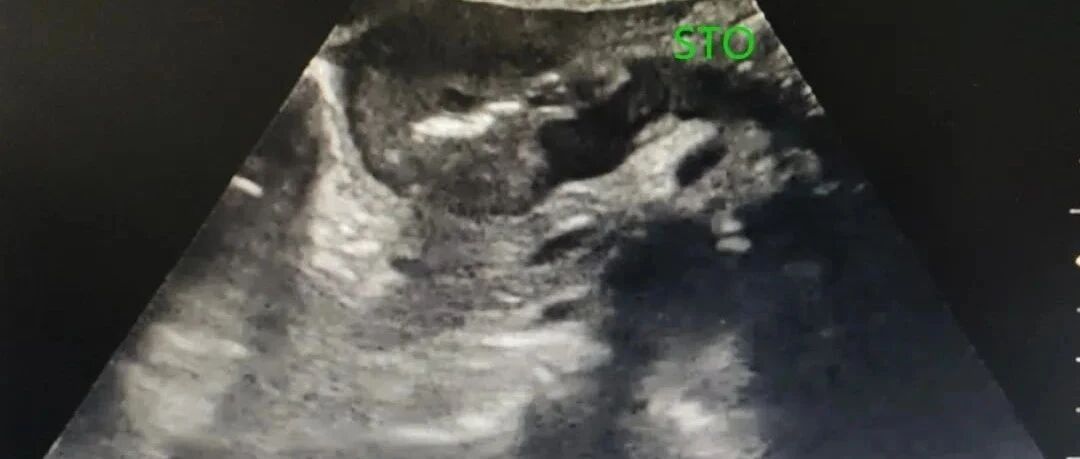

经典病例:遇到这样的胃窦癌,你能确诊吗? 丁香园超声时间 · 公众号 · 医学 · 1 年前 · |